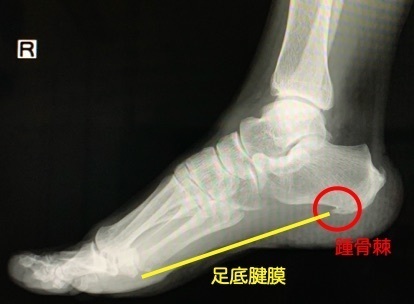

レントゲン検査

・腱の炎症のため、レントゲン検査では骨に異常がないことが多いです。

・繰り返し足底腱膜が踵の付着部を引っ張るストレスがかかっているため、棘(踵骨棘)が出来る方がいます。踵骨棘は、レントゲンにうつります。

棘(踵骨棘)は足底腱膜にストレスがかかっていることを意味します。

※骨の変形や他の疾患との鑑別するためには必要な検査です。